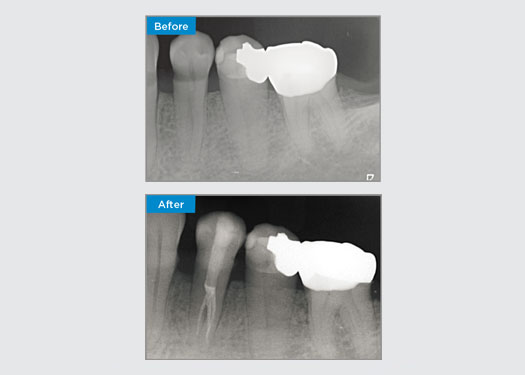

Der Patient stellte sich mit einer asymptomatischen apikalen Parodontitis an Zahn 34 vor. Auf dem präoperativen Röntgenbild war Zahn 34 mit zwei sichtbaren Wurzeln zu erkennen. Ein DVT-Scan bestätigte jedoch, dass es sich um einen dreifach verwurzelten Prämolaren handelte und dass sich die Kanäle in der Mitte der Wurzel in drei Kanäle aufteilten. Für diesen empfindlichen Zahn ist eine sorgfältige Feilenauswahl entscheidend.

In dieser Situation ist die Erhaltung der Zahn-/Wurzelstruktur von entscheidender Bedeutung, um das Risiko von Vorsprüngen, Verschiebungen, Abrissen, Perforationen und Wurzelfrakturen zu verringern. Fallauswahl, Diagnose und Behandlungsplanung sind wichtig. Die Auswahl von endodontischen Feilen, die flexibel und effizient sind und die natürliche Wurzelanatomie respektieren, ist entscheidend.